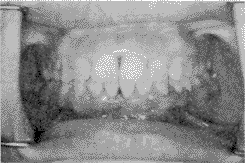

典型病例: 王某某,女,15 岁,检查:上下第二磨牙均已萌出建立咬合,左右第一磨牙为中性关系,上下牙列基本整齐,上切牙唇倾,有散在间隙,下前牙咬及上前牙舌侧牙龈,切牙覆盖9 mm,下牙弓spee 曲线陡峭,开唇露齿,面下1/3 过低,下颌角低平。矫治过程:第一、二磨牙粘固带环,其它牙齿贴方丝弓托槽,直径0.41 mm镍钛圆丝启动,戴前牙平导板(后牙离开4 mm),逐步更换0.46 mm镍钛圆丝及0.41 mm×0.56 mm,0.46 mm×0.63 mm 镍钛方丝整平牙弓,并开始进行后牙颌间“W”形牵引,6 个月后前牙覆

正常,开始内收上切牙,进行咬合调整,15 个月后完成矫治(见图2)。矫治前后头影测量结果见表2。

矫治前 矫治后

图2 深覆

矫治前后咬合正位像